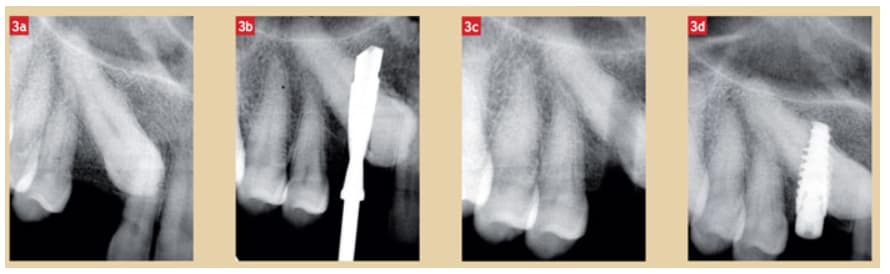

https://www.lefildentaire.com/articles/analyse/experience/appel-a-contribution-2-ans-apres-chose-promise-chose-due/

https://www.lefildentaire.com/articles/clinique/implantologie/implant-et-canine-incluse-nouvelle-approche/

En effet c'est un peu petit. J'ai quand même l'impression qu'ils ont réussi à éviter l'endodonte, et que seule la face palatine de l'implant est en partie dans la canine, tout le volet vestibulaire étant bien osseux.

Voilà ce que j’ai fait finalement. Hokusai l’intérêt c’est qu’il va avoir aussi trois couronnes :)